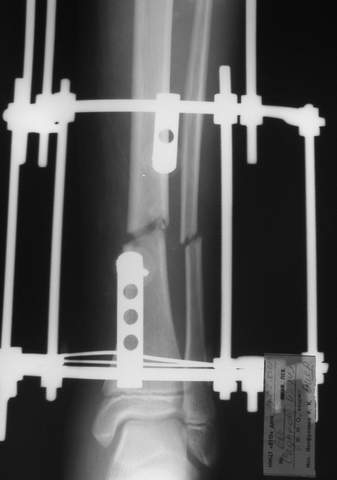

В аттачтах №№ 1 и 2 - примеры, когда 2 кольца не позволили послеоперационно

исправить смещение фрагментов большеберцовой (по ширине и вальгусное).

А казалось бы (#2) - поиграй на штангах и все влетит.

Оперировал не я

:-)